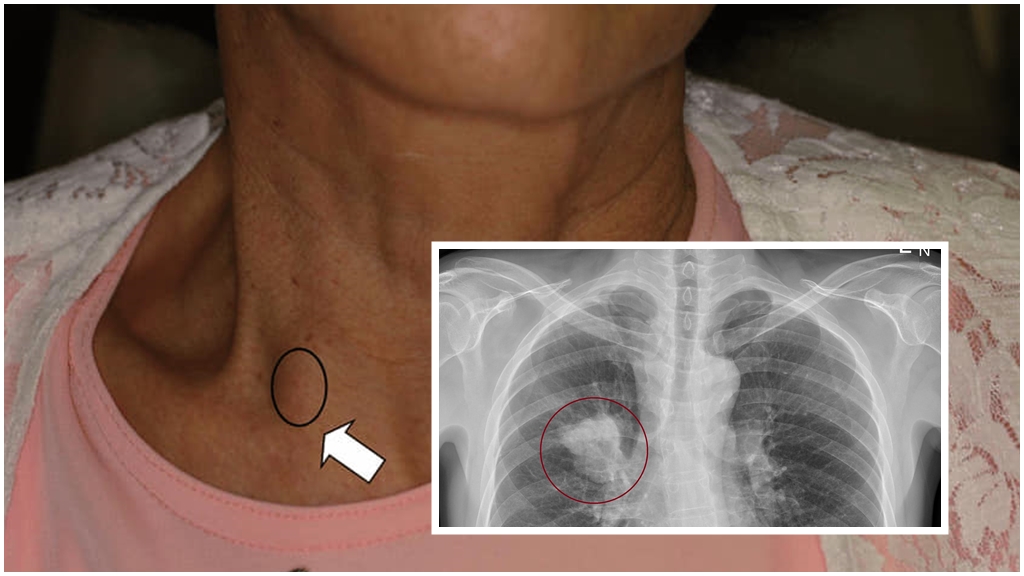

73歲務農的林先生,因體重莫名減輕5~6公斤,合併虛弱無力,轉診至台北榮總,發現患有C型肝炎合併肝硬化,且肝臟長一顆6公分腫瘤,胃鏡檢查發現食道長出6條靜脈曲張(2條中型、4條小型),屬於高危險性出血的食道靜脈曲張。經討論後,為了預防食道靜脈曲張出血,在民國108年接受結紮術,後續做完8次完全根除,也接受肝癌手術,至今沒有發生食道靜脈曲張出血及腫瘤復發狀況。

▲林先生術前食道靜脈曲張嚴重鼓起(左圖星號位置),術後完全正常。(北榮提供)